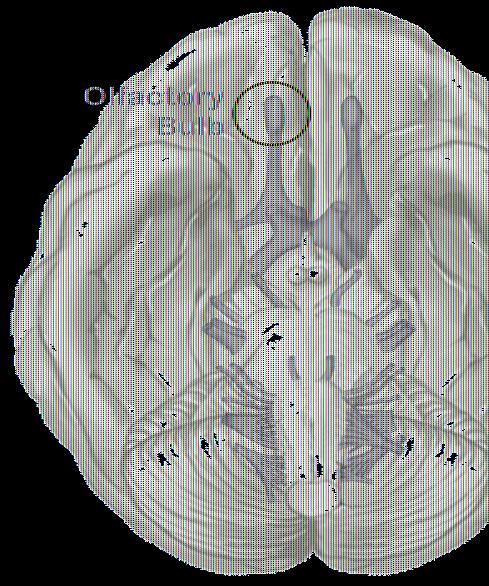

The olfactory bulb transmits information from the nose to the brain. Credit: Roberto Lent

The isotropic fractionator, a fast and reliable technique previously developed by a group of researchers at Federal University of Rio de Janeiro, measures the absolute number of cells in a given brain structure such as the olfactory bulb, which is the first brain region to receive olfactory information captured by the nostrils.

Using this technique, a group of researchers led by Prof. Roberto Lent from the Institute of Biomedical Sciences at the Federal University of Rio de Janeiro and the National Institute of Translational Neuroscience, Ministry of Science and Technology in Brazil, has finally found biological evidence in the brains of men and women that may explain the olfactory difference between genders.

The group examined post-mortem brains from seven men and 11 women who were all over the age of 55 at the time of death. All individuals were neurologically healthy and none worked in professions requiring exceptional olfactory abilities, such as coffee-tasting or professional cooking. By calculating the number of cells in the olfactory bulbs of these individuals, the group (that also included researchers from the University of São Paulo, the University of California, San Francisco, and the Albert Einstein Hospital in São Paulo) discovered that women have on average 43% more cells than men in this brain structure. Counting neurons specifically, the difference reached almost 50% more in women than men.